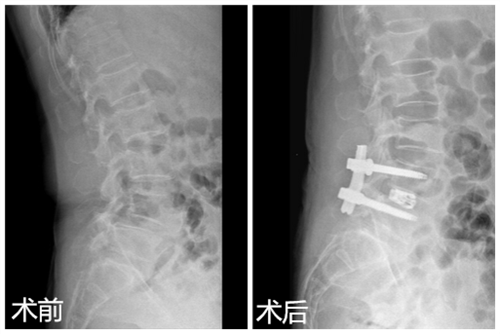

患者刘女士,60岁,腰部疼痛伴双下肢步行受限半年,近1个月出现间歇性跛行。曾到多家医院求治均效果不佳,后慕名来到临床医学院/附属医院疼痛科求医,门诊医师经过检查后诊断为腰椎间盘突出症伴腰椎Ⅱ度滑脱,椎管狭窄,并建议住院治疗。疼痛科医疗团队为患者进行了仔细的体格检查及影像学评估,做好充分的术前准备后,在DSA引导下成功为患者实施椎间孔镜辅助Endo-LIF腰椎融合术。术后第二天,患者腰部疼痛明显缓解,四天后下地活动,受限恢复正常,患者和家属十分满意。

对于腰椎间盘突出症伴腰椎滑脱,传统的治疗方法是开放手术,由于创伤大,风险高,并发症相对较多,很难为患者和家属接受。融合技术作为脊柱治疗中最重要的技术,逐渐发展为从传统开放走向微创。椎间孔镜辅助Endo-LIF腰椎融合术是将内镜技术、融合技术及经皮内固定技术相结合,该技术是经过腰椎后外侧融合,无需像传统开放手术那样对关节突进行切除,无需干扰腰椎后方的肌肉,对患者腰部解剖结构及稳定性破坏极小,在实现手术切口最小化的同时,达到真正意义上的微创。该技术具有切口小、风险低、创伤小、并发症少的优势,很容易被患者和家属所接受,也是以后脊柱外科发展的方向。